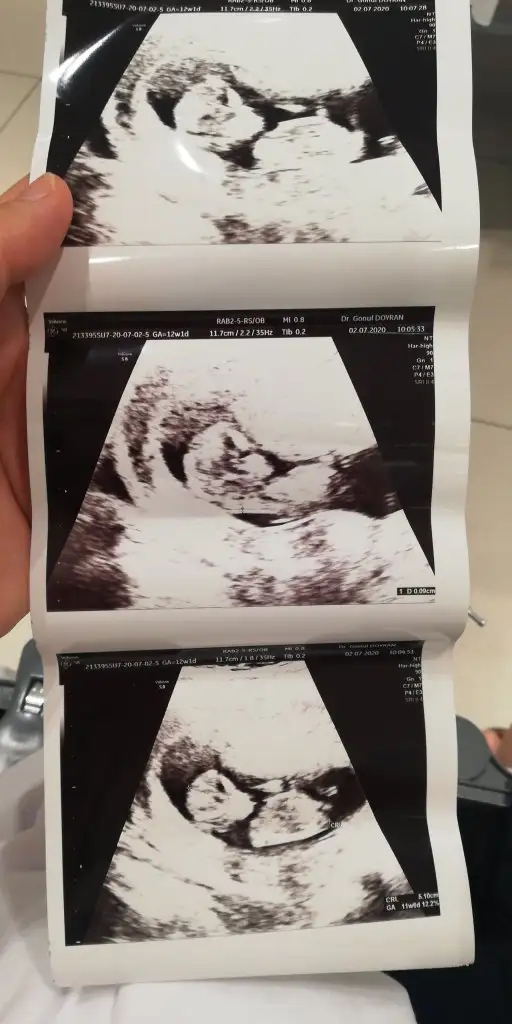

Ikra meyra Ikra meyra bebeğim 12+1 haftalik doktor kıza benzetti sizde bakabilir misiniz

Eklentiler

• Screenshot_20200707-141724_Gallery.webp

Screenshot_20200707-141724_Gallery.webp

7,9 KB · Görüntüleme: 79

• Screenshot_20200707-141709_Gallery.webp

Screenshot_20200707-141709_Gallery.webp

10,9 KB · Görüntüleme: 93